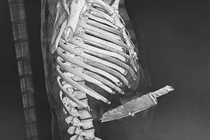

(khoahocdoisong.vn) - Khoa Cấp cứu, Bệnh viện Chợ Rẫy TPHCM tiếp nhận một bệnh nhân trong tình trạng nguy kịch với vết thương ở ngực trái. 15 phút sau, bệnh nhân được đưa vào phòng mổ cấp cứu.

(khoahocdoisong.vn) - Các bác sĩ Bệnh viện E vừa cứu sống ngoạn mục một bệnh nhân nam (35 tuổi, Hà Nội) bị dao đâm xuyên từ phải sang trái, từ dưới lên trên vùng cuống họng.